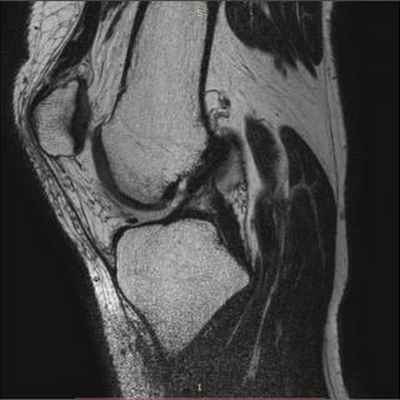

на фиг.5 - рентгенограмма коленного сустава в прямой и боковой проекции больного с начальными признаками остеоартроза; на фиг.6 - магнитно-резонансная томография коленного сустава больного, где отсутствует передняя крестообразная связка и наружная боковая связка; на фиг.7 - магнитно-резонансная томография коленного сустава больного, где показана восстановленная передняя крестообразная связка и наружная боковая связка; на фиг.8 - полное сгибание коленного сустава через три месяца после операции; на фиг.9 - стабильность коленного сустава через три месяца после операции.

На МРТ левого коленного сустава до операции в боковой и фронтальной проекциях - отсутствие ПКС и дефект НБС (Фиг.6).